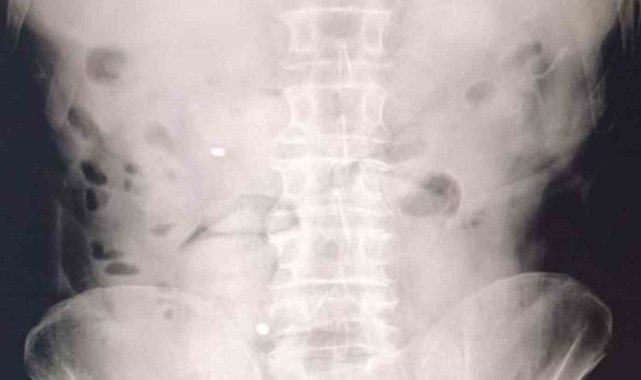

Uşak'ta takside yolcu olarak bulunan İran uyruklu 2 şüphelinin midesinden ve bağırsaklarından 93 kapsül halinde 1 kilo 70 gram metamfetamin ele geçirildi. Olayla ilgili 2 şüpheli tutuklandı.Uşak İl Emniyet Müdürlüğü Narkotik Suçlarla Mücadele Şube Müdürlüğü ekipleri, "Uyuşturucu Madde Ticareti" ile mücadele çalışmaları kapsamında yürütülen çalışmalar ve takipler neticesinde il merkezinde bir taksiyi durdurdu. Takside yolcu konumunda bulunan İran uyruklu D.G. ve A.C. gözaltına alındı.Şüphelilerin hastanede yaptırılan kontrolleri ve çekilen röntgen filmleri sonucunda mide ve bağırsaklarında çok sayıda uyuşturucu madde içeren kapsül bulunduğu tespit edildi. Hastanede kontrollü şekilde gözetim altında tutulan şüphelilerden tıbbi müdahaleler neticesinde toplam 93 parça halinde 1 kilo 70 gram metamfetamin ele geçirildi.Operasyon kapsamında "Uyuşturucu veya Uyarıcı Madde Ticareti" suçu çerçevesinde adli işlem yapılan 2 şüpheli, sevk edildikleri adli mercilerce tutuklandı.

Midelerinden 1 kilo 70 gram metamfetamin çıktı

Uşak'ta takside yolcu olarak bulunan İran uyruklu 2 şüphelinin midesinden ve bağırsaklarından 93 kapsül halinde 1 kilo 70 gram metamfetamin ele geçirildi. Olayla ilgili 2 şüpheli tutuklandı.